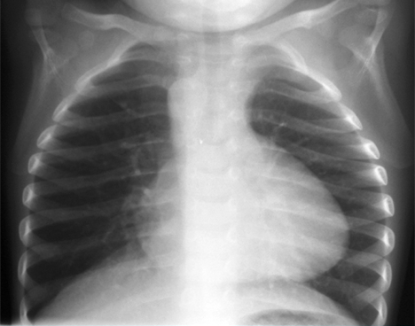

Patient was placed on 2L O2 by nasal cannula and her SpO2 increased to 97% at rest, she would stay at this saturation unless made to be upset by staff. A chest x-ray was ordered and COVID/RSV/Flu swab was run. The swab came back negative and her chest x-ray showed “Boot-shaped cardiac morphology, often described in the setting of Tetralogy of Fallot. Correlation with echocardiography and patient history might be considered. Mildly to moderately increased perihilar markings, but no focal consolidation or pleural effusion.”

The characteristic findings seen here are:

- Hyperinflated lungs

- Decreased pulmonary vasculature from lack of pressure through the pulmonary arteries

- The aorta is concave to the right due to its malposition

- There is a boot shape to the heart secondary to RV enlargement

In our patient, she had an upturned heart with boot like shape, suggestive of ToF but did not have any of the other signs like lack of peripheral vascularity or hyperinflated lungs. We did do a bedside ultrasound and thought we witnessed some RV hypertrophy but were not able to find other parts of the heart to try and compare them to the above images to further evaluate ourselves. Since the patient was having intermittent episodes of hypoxia given her relatively normal chest x-ray, a decision was made to transfer to a tertiary facility for further evaluation.